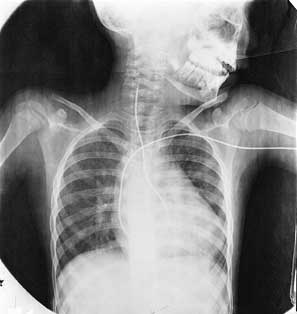

يحدث تصلب الشرايين التاجية عادة على مدى سنوات عديدة، رغم أن الأطباء وجدوا لُويحات في الشريان التاجي في بعض صغار السن من الجنود الذين قتلوا في المعارك. ولكن الأعراض غالبًا ما تظهر بعد سن الخمسين أو أكثر في بعض الأحيان. وتكون النوبة القلبية أولى الأعراض، وأحيانًا يحدث الموت المفاجئ. وعلى أية حال فإن الأعراض المبكرة المشابهة قد تكون ألمًا في الصدر يعقب تمارين رياضية أو أي نشاط آخر يجعل القلب يعمل أكثر من المعتاد. ويسمي الأطباء مثل هذا الألم بالذبحة الصدرية أو الذبحة. والشرايين التاجية الضيقة تغذي القلب بأكسجين أقل، مما يتسبب في الألم عندما يعمل القلب بطاقة أكثر. وبعد أن تتوقف التمارين أو ينتهي المجهود يتوقف الألم. وتزداد الذبحة إذا تركت من غير علاج، وغالبًا ما يشتكي المريض من ألم حتى وهو في حالة الراحة التامة. يشخص الأطباء أمراض الشريان التاجي بدراسة حالة المريض العامة والأمراض السابقة التي أصابته. ويسجلون تاريخ أي ذبحة أو نوبة قلبية أو وجود أي عوامل خطر. وقد يكشف الفحص العام عن وجود أسباب وعوامل خطر مثل ارتفاع ضغط الدم أو عطب في القلب. يستعمل الأطباء آلة تسمى مرسمة كهربائية القلب لمعرفة أي عطب في القلب أو أي اضطرابات في انتظامه. وتعطي هذه الآلة تخطيطًا يسمى رسم كهربائية القلب، يوضح النشاط الكهربائي لعضلة القلب. وتسجل الدفعات على ورق متحرك يوضح نشاط القلب الكهربائي على شكل سلسلة من الخطوط المموجة أو المتعرجة. وتمثل التعرجات الأساسية انقباض البطين والتعرجات الفرعية تمدد البطين وانقباض وتمدد الأذين. وتؤخذ معظم رسومات القلب للمريض وهو مستلقٍ، ولكن بعض الأطباء يرسم القلب للمريض وهو يؤدي بعض التمارين الرياضية. ومثل هذا التخطيط يوضح ما إذا كان القلب مريضًا حتى وإن لم يشك المريض من ألم، ويوضح إذا كان القلب يتلقى كمية كافية من الأكسجين أثناء التمارين الرياضية القاسية أم لا. يستعمل الأطباء أيضًا طريقة أخرى تسمى التصوير النَّوَوي الشُّعاعي، لتعرف مرض الشريان التاجي. يحقن الطبيب مادة مشعة في دم المريض ويستطيع أن يرى المادة على شاشة أثناء انتشارها في عضلات القلب. والمساحة التي لا تتلقى دمًا تظهر خالية على الصورة. ويستعمل الأطباء التصوير النووي الشُّعاعي عادة مع رسم كهربائية القلب تحت الإجهاد. وإذا كان هناك شك في أسلوب التشخيص العادي فإن الأطباء قد يفضلون القثطرة القلبية، ثم يعقبها تخطيط الأوعية التاجية. وهنا يدخلون أنبوبًا مرنًا طويلاً يسمى القثطار عن طريق وعاء دموي كبير عادة ما يكون شريانًا في منطقة التقاء الفخذ مع الجذع، ويدفعون القثطار إلى حيث يبدأ الشريان التاجي ويحقنون صبغة. بهذه الطريقة يمكن رؤية الشرايين من الداخل ـ ويمكن تسجيلها على فيلم أشعة سينية وتسمى الصورة الوعائية. وهذا الاختبار يُظهر حالة الشرايين التاجية بوضوح. وقد توضح الصورة الوعائية للشريان التاجي وجود إصابة طفيفة أو ربما الموت في بعض الأحيان. ولهذا يجريها الأطباء فقط في الحالات التشخيصة المعقدة.

وزودت الأشعة السينية العلماء في السابق بأول صورة عن القلب الحي. أما طريقة النظر في أجزاء القلب الداخلية فقد بدأت مع قثطرة القلب في العام 1929. وكان الطبيب الألماني الشاب ڤرنر فورسمان رائدًا في هذا المجال حيث جرب في نفسه مرور أنبوب مطاطي في البطين الأيمن لقلبه، وبذلك أعطى أول صور وعائية قلبية (صور بالأشعة السينية لغرف القلب والأوعية الدموية). وحاز جائزة نوبل في الطب نظرًا إلى تجربته الرائدة في طب القلب التشخيصي.